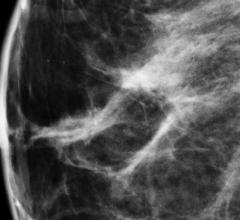

Mammography is a breast imaging technique that uses X-rays to diagnose and locate tumors of the breasts.

Mammograms have long been the first line of defense in detecting breast cancer, which continues to be one of the most ...